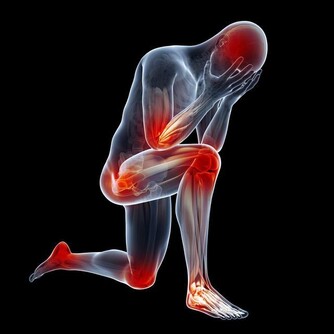

慢性腎炎腰疼痛,陳舊性扭傷、腰痛、腎虧、腰酸脹痛,

長年發作性腰痛,諸藥無效的無名頑疾腰痛等症,

腰痛病是常見病,社會上各行業的人員中,

有80%的人患有程度不同的腰痛病,最常見的腰痛病有急性腰部軟組織損傷症。

主要症有:屈伸活動受限,局部有明顯壓痛或腫脹,

疼痛可反射至胸背下部、下腹部、上臀部、兩側大腿前面、外側或後面直至踝部,

同時因天氣變化,甚至病狀加重。

醫學家認為風濕、腎虛、損傷是導致腰痛的主要因素。